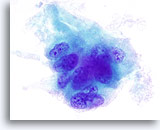

Negatief voor maligne cellen consistent met Hashimoto-thyroïditis

Wij zijn er achter gekomen dat ThinPrep niet optimaal is voor de diagnose van thyroïditis.[6] Hashimoto-thyroïditis wordt gekenmerkt door lagen of groepen folliculaire cellen met variërende mate van Hürthle-celveranderingen op een achtergrond van variërende aantallen lymfocyten en plasmacellen met incidenteel lymfoïde en folliculaire kernaggregaten. Omdat lymfocytisch/Hashimoto-thyroïditis een veelvoorkomende bevinding is bij de schildklier, is de monsterverzameling essentieel bij het uitsluiten van andere eveneens voorkomende en meer belangrijke laesies.